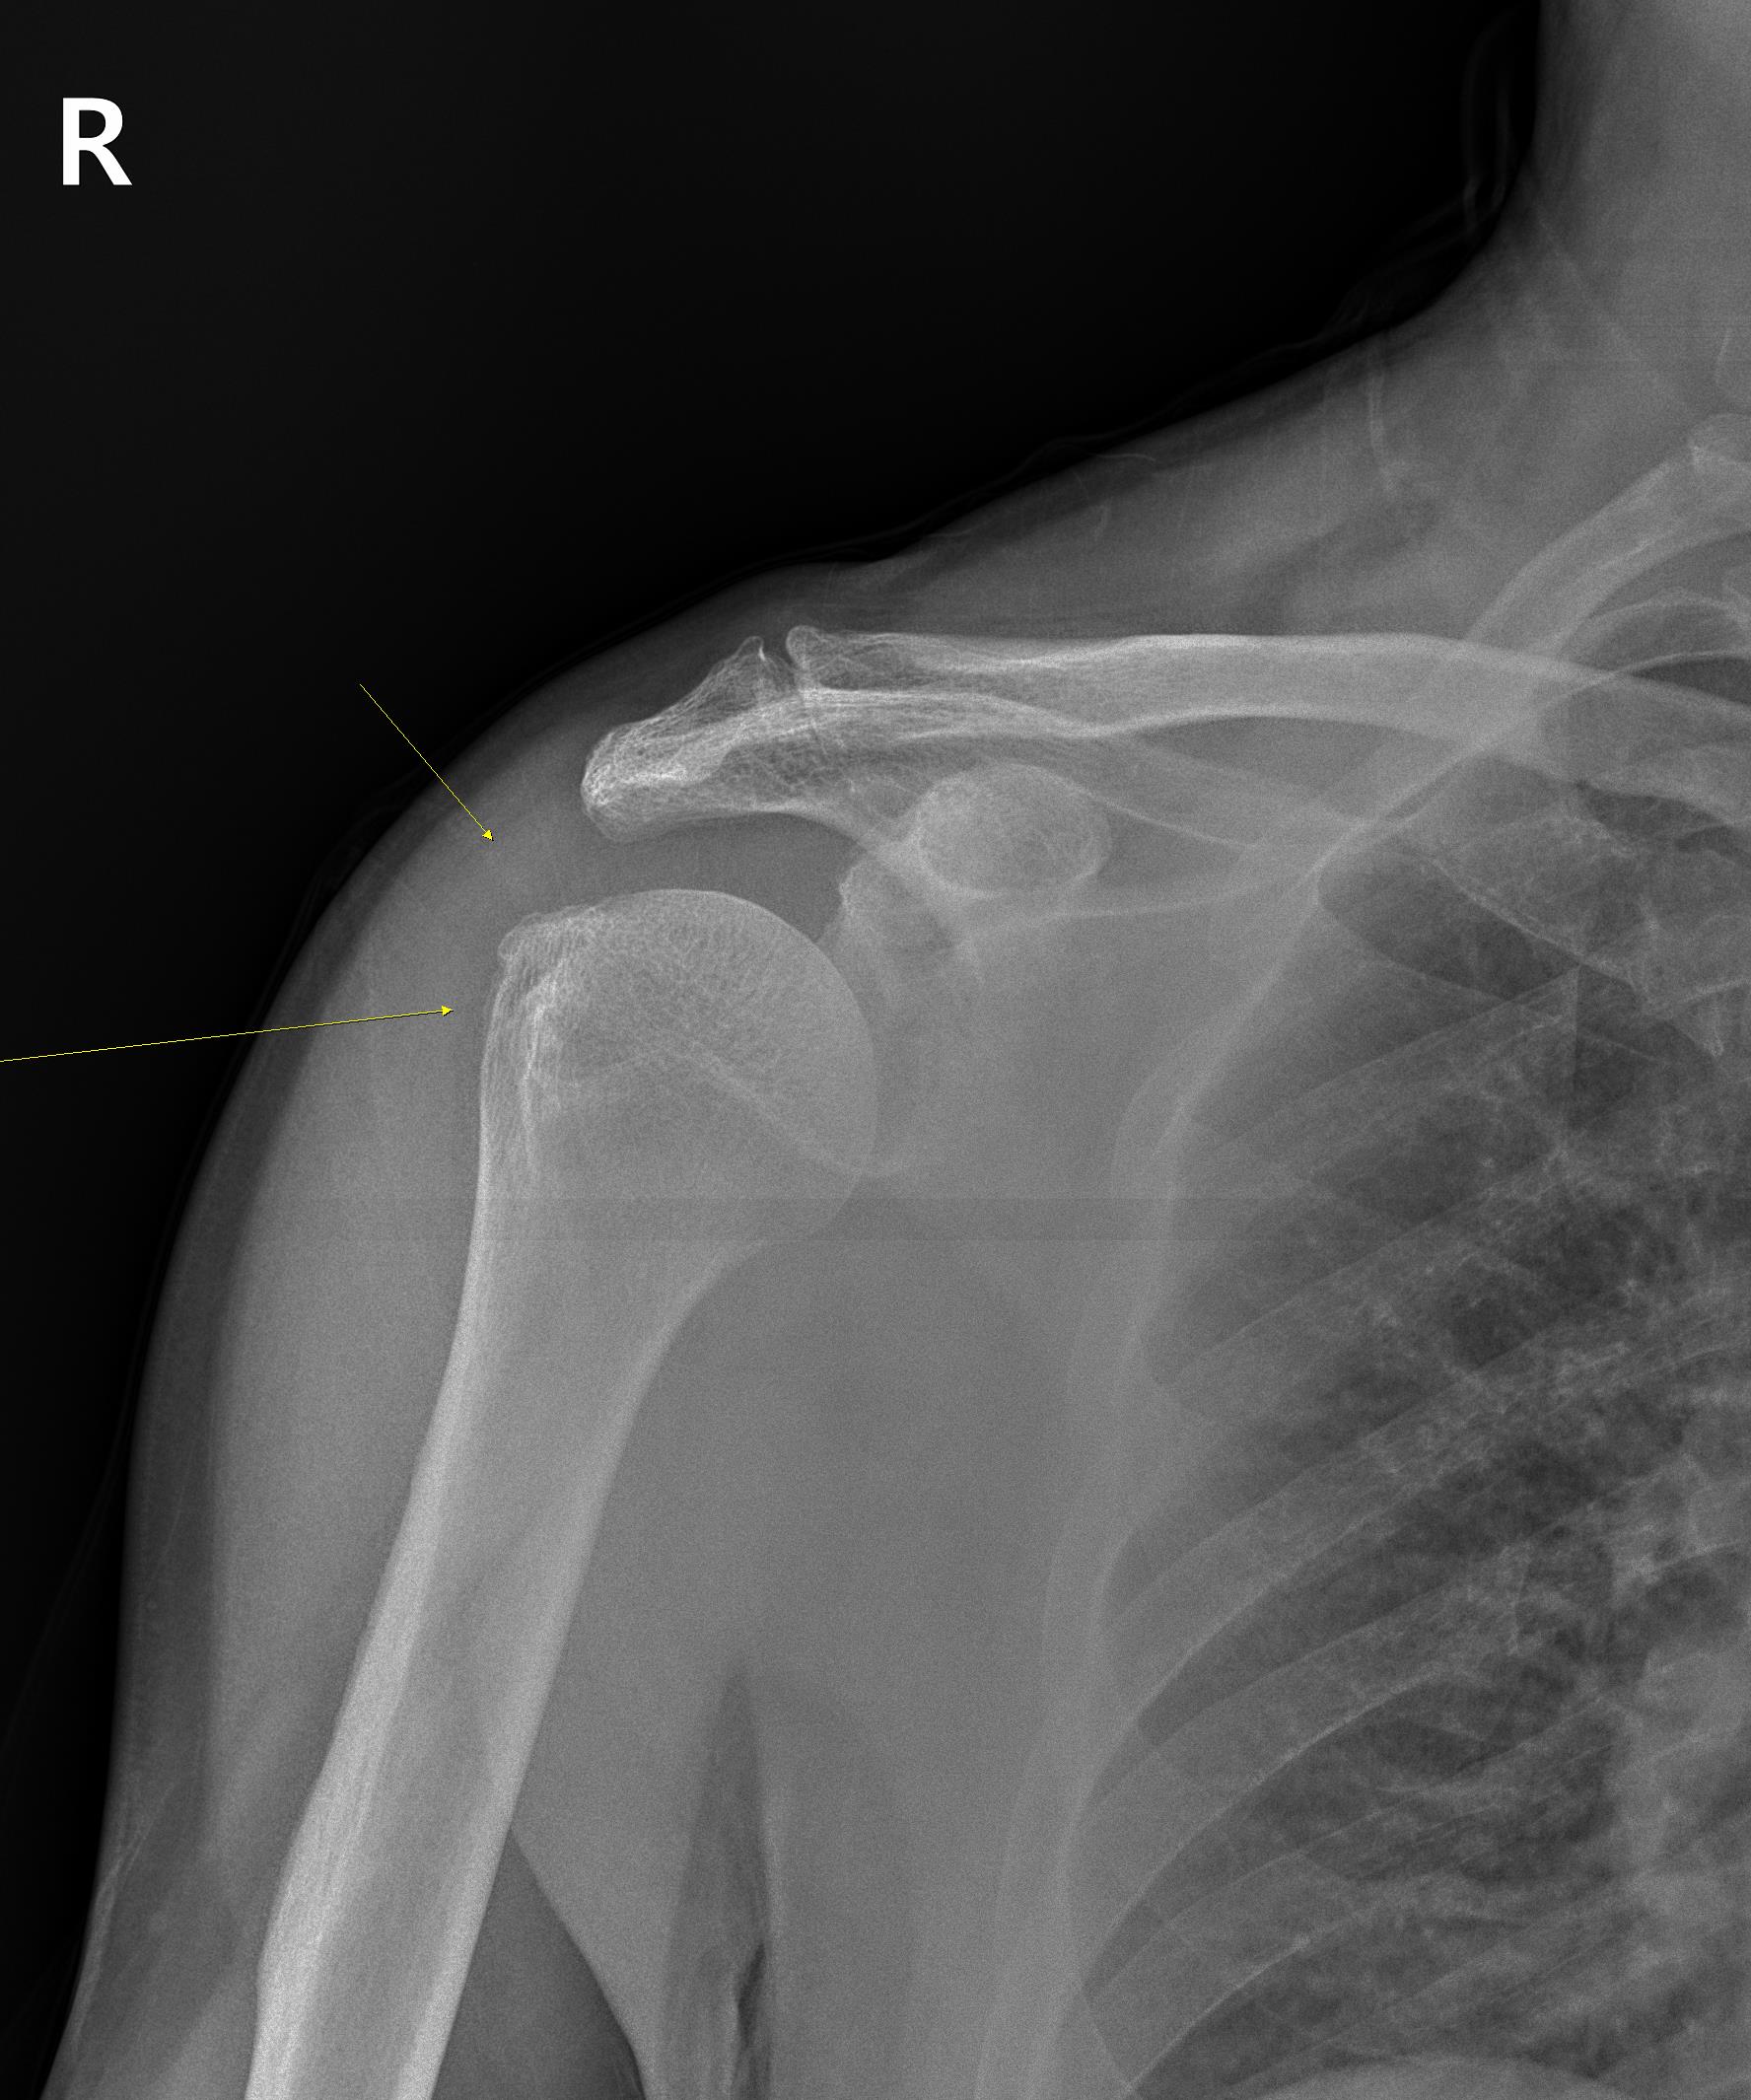

안녕하세요 박상준원장입니다. 아주 오랫만에 블로그에 글을 올리네요... 오늘은 크로스핏 하다가 어깨가 아파서 온 환자 이야기를 좀 해볼까 합니다.나 : 어디가 아프세요?환자 : 우측 어깨가 아픕니다나 : 언제 무슨일이 있으셨어요?환자 : 제가 웨이트 트레이닝을 시작했는데.... 벤치 프레스랑 턱걸이 하면서 통증이 생겼습니다 웨이트 트레이닝을 하면서 어깨가 아파졌다는 환자, 우선 x-ray를 찍었습니다. 사진을 보니 우측 상완골 대결절 부위에 골극이 보입니다. 골극(bone spur)은 쉬운말로 '뼈가 자라있다'라고 말하곤 하는데요... 뼈의 특정 부위에 오랫동안 염증이 반복되는 등의 자극이 반복되면 관찰되는 소견입니다.나 : 어깨가 아프신게 처음이에요? 이전에도 약간씩 불편감이 있을셨을거 같은데요...환..